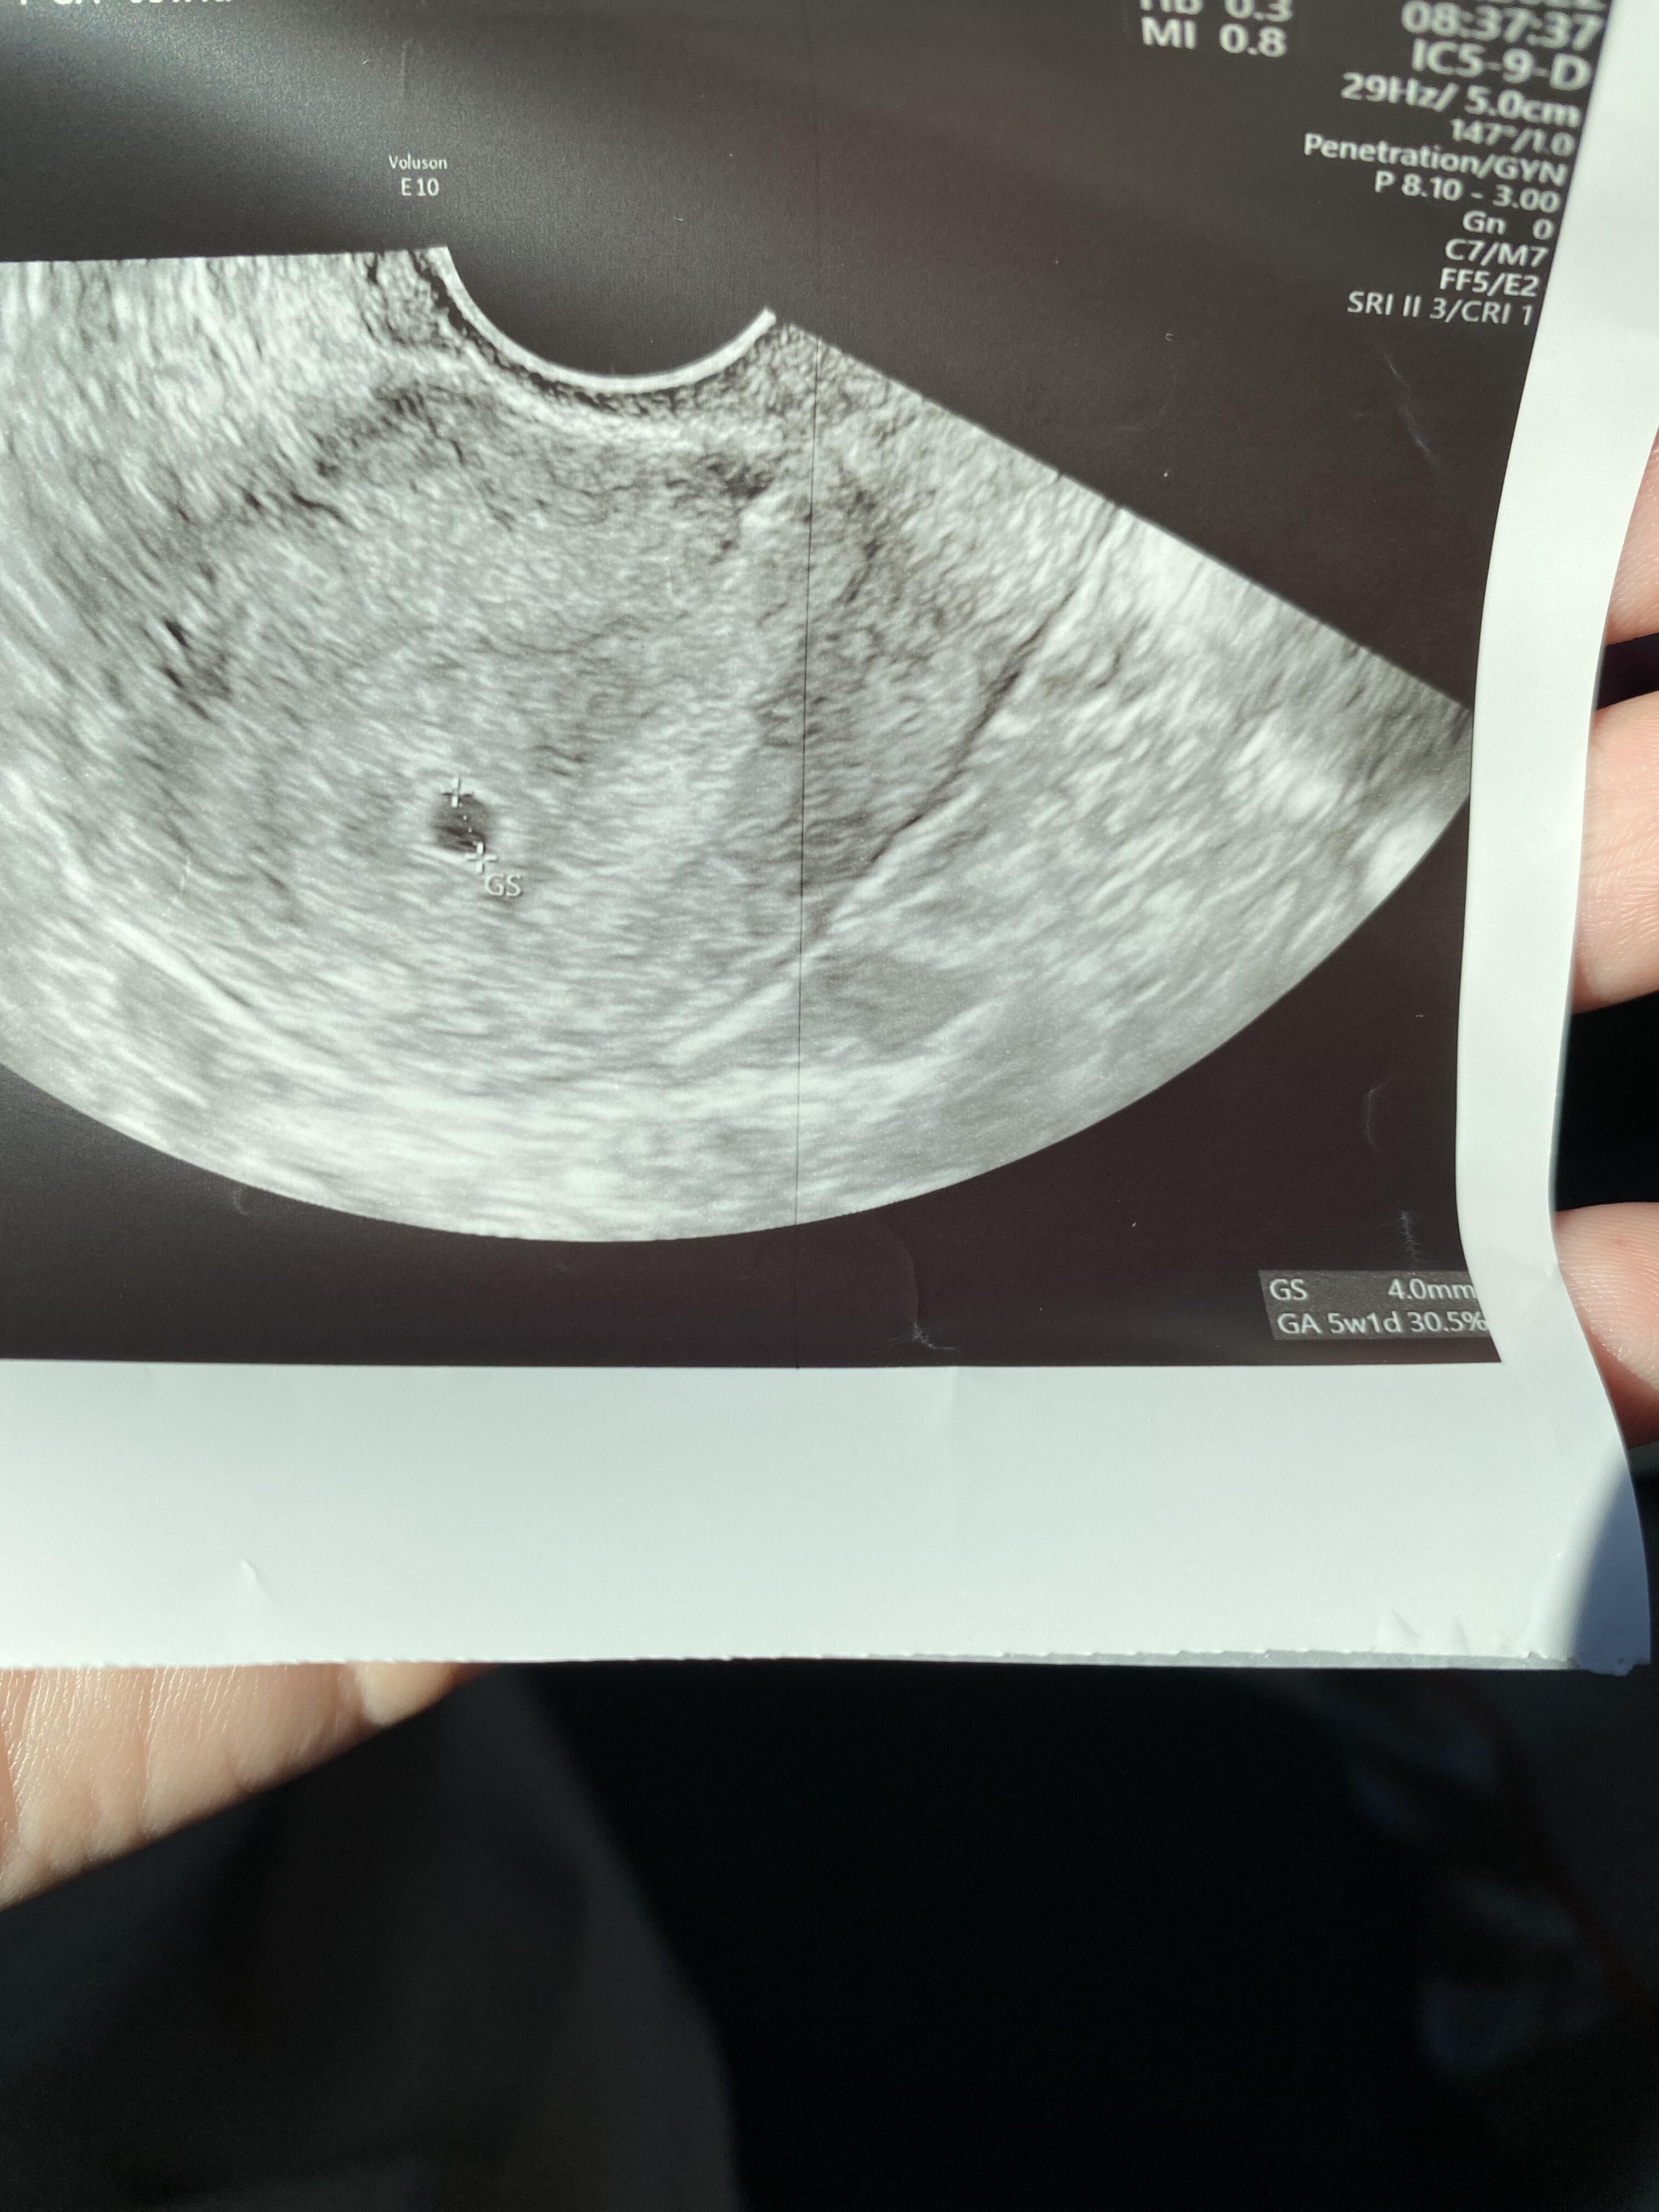

Pęcherzyk jest, wyglada prawidłowo - ta beta to mogłabym i wpadka labuNa tym pierwszym z twgo wychodzi,ze terminu się pokrywają. U mnie były ja początku zawirowania z beta, bo miałam jeden przyrost ka pozimie 47% . Potem odbiła i teraz się boje, ze coś jest nie tak.

Tak to u mnie wyglada. W dniu usg termin z om był 5+1

Super przyrost. Ja ostani robiłam w poniedziałek. Jutro muszę zrobić tarczyce i przy okazji oznacza po raz ostani bete, ale boje się przez te zawirowaniaMam wyniki betyz 498 na 1860 po 72h